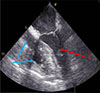

CPB cannulas were connected to the VA ECMO circuit, and the superior and inferior vena cavae were snared to minimize a blood flow to the right heart and the pulmonary artery (Figure 3). In this ECMO configuration, end-diastolic volumes of the right ventricle (RV) and left ventricle (LV) were 16 mL and 38 mL, respectively (Figure 4).

Figure 4 Transesophageal echocardiography picture. The right chambers of heart are collapsed due to snared superior and inferior cava veins (1, blue arrows); reduced end diastolic volume of left ventricle (2, red arrow). |